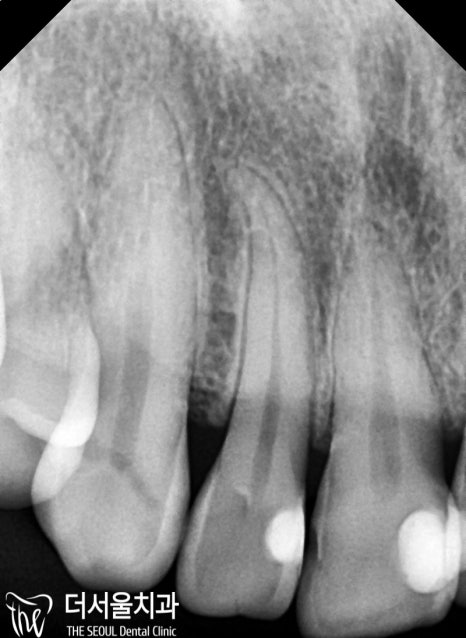

군데군데 거뭇하게 보이는 우식이 관찰되었는데요.

치경부 마모가 나타나 있었기 때문에

이시림도 동반되고 있었습니다.

치아 사이에 나타나 있던 우식!!!!

인접면에 나타난 우식은

겉으로 봤을 때 티가 잘 나지 않기 때문에

조기에 발견하는 것이 쉽지 않습니다.